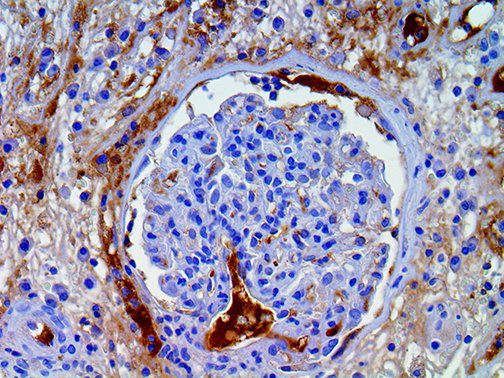

This activation induces inflammatory monocytes to highly express IL-6, starting a localized and then systemic cascade effect that results in hyperproduction of IL-6, which accelerates the inflammatory process. Because IL-6 also increases vascular permeability, excessive levels cause blood vessels to become very leaky. This, along with clotting factors released from vascular endothelial cells, stimulates the coagulation cascade, resulting in microthrombosis (tiny clots), which leads to ischemia and tissue death of the kidney, intestines, heart, liver, brain and extremities.